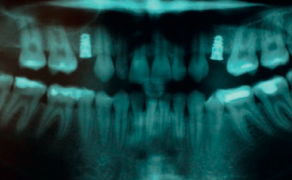

STRESZCZENIE: W pracy przedstawiono wyniki zespołowego leczenia ortodontyczno-chirurgiczno-protetycznego pacjenta z hipodoncją. Hipodoncja należy do zaburzeń rozwojowych dotyczących braku zawiązków zębów stałych i mlecznych (brak jednego lub kilku zębów). Patologia ta powoduje problemy czynnościowe i estetyczne będące głównym powodem, dla którego pacjenci decydują się leczyć. Opisywany przypadek dotyczy pacjenta z brakiem zębów 12 i 22, u którego zastosowano leczenie wieloetapowe. Uczestniczyli w nim specjaliści kilku kierunków stomatologicznych. Wdrożenie nowoczesnych metod chirurgicznych pozwoliło na zastosowanie procedur implantoprotetycznych mimo trudnej sytuacji klinicznej. Pacjent został zaopatrzony w uzupełnienia stałe. Wykonane uzupełnienia implantoprotetyczne zostały w pełni zaakceptowane przez pacjenta. Poprawiły nie tylko funkcję żucia i mowy, ale również samopoczucie pacjenta.

SUMMARY: The paper presents the results of team orthodontic, surgical and prosthetic treatment of a hypodontic patient. Hypodontics is a developmental disorder involving the absence of permanent and milk tooth buds (one or more [...]